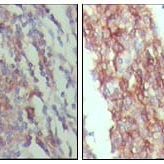

Product Image |

| IHC | 1/200 - 1/1000 |